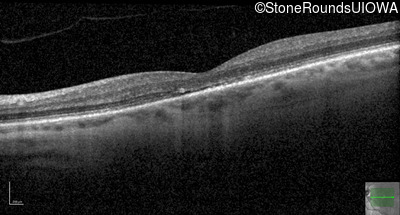

The clinical features supporting the diagnosis of blue cone monochromacy in this patient include: stable reduced acuity, photophobia and very poor color vision since early childhood, a normal fundus appearance, normally sighted parents and three similarly affected male relatives on the maternal side of his family.

Age at visit: 30 years